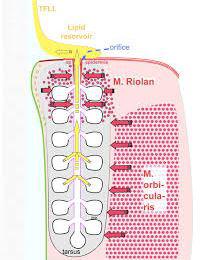

One of the main causes of MGD may well be tied to a patient’s blink rate. Theories suggest that the lack of a full or complete blink can result in less pumping activity of the lower eyelid meibomian glands, which are responsible for 78% of the oils in the tear film.

The pumping action occurs during a blink because a muscle named the Riolan muscle surrounds the meibomian glands and is only activated when the eyelids come together during a blink. A partial blink or an incomplete blink will not activate the Riolan muscle.

Eyelid Exercises do two things: 1. They make up for missed blinks and 2. They strengthen the Riolan muscle and make our blinks more productive to release more oil from the meibomian glands.